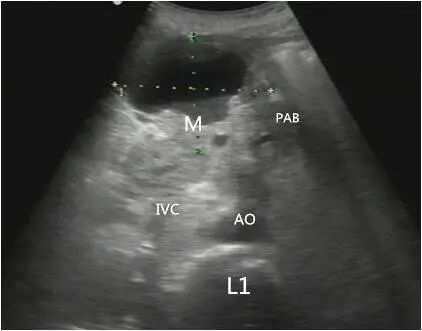

胰体尾部癌

第二种表现为胰腺内肿物不规则或有分叶状的团块回声,肿块边界不清,轮廓不整,向周围组织呈蟹足样或锯齿样浸润。

第三种表现为较小的肿块,内部大多数为均匀低回声,后方声衰减不明显;较大肿瘤呈混合回声,后方回声衰减,也可以看到坏死液化的无回声区。